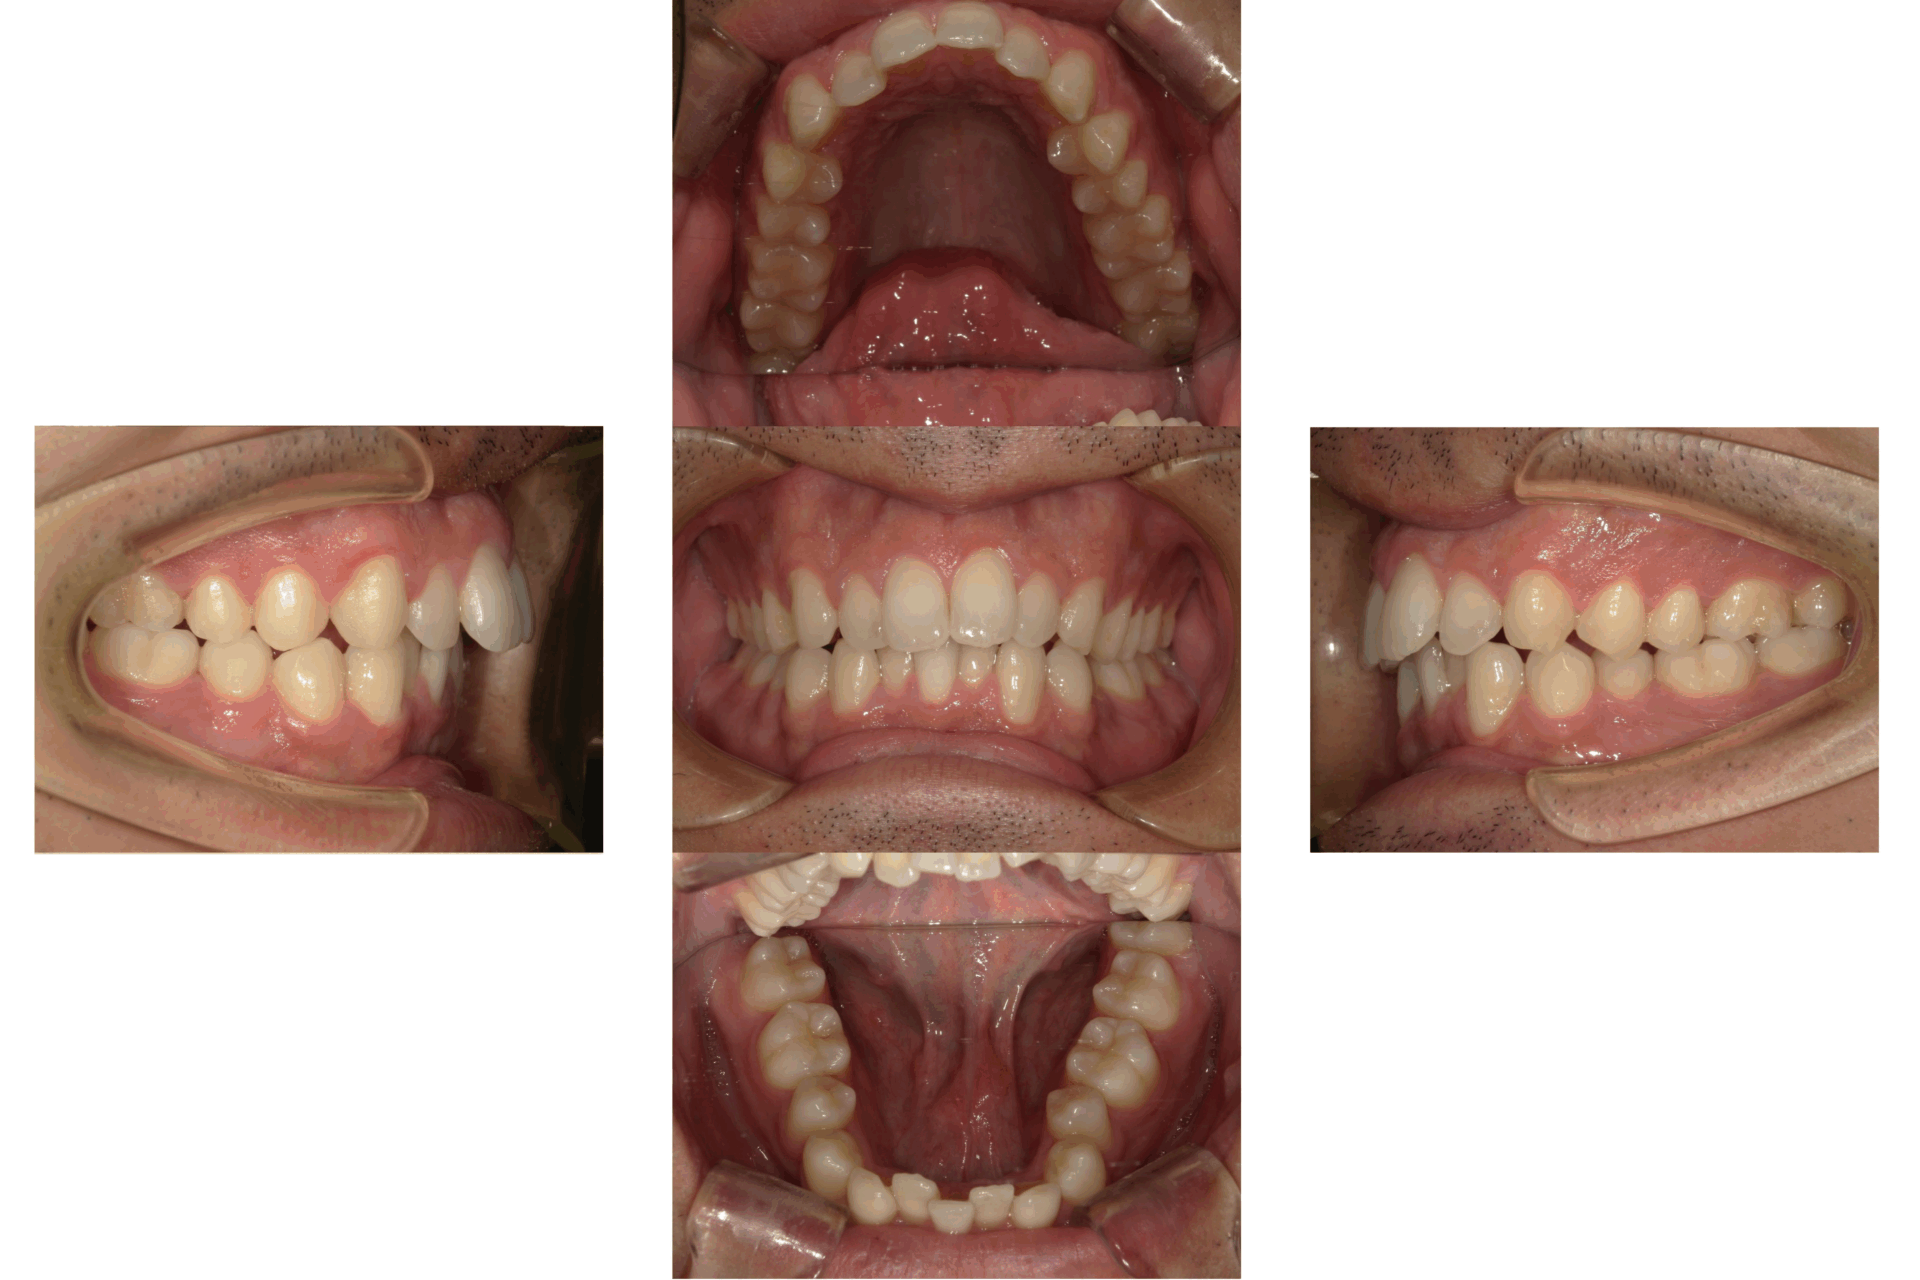

20代、女性、ワイヤー

| 施術内容 | 主訴:口ゴボが気になる。 詳細:ワイヤー矯正での歯並び改善 口元がかなり変化し、とても満足された症例です。 |

| 治療期間 | 16ヶ月(3/24現在 治療終了) |

| 費用 | ワイヤー矯正 60万円(税込660,000円) |